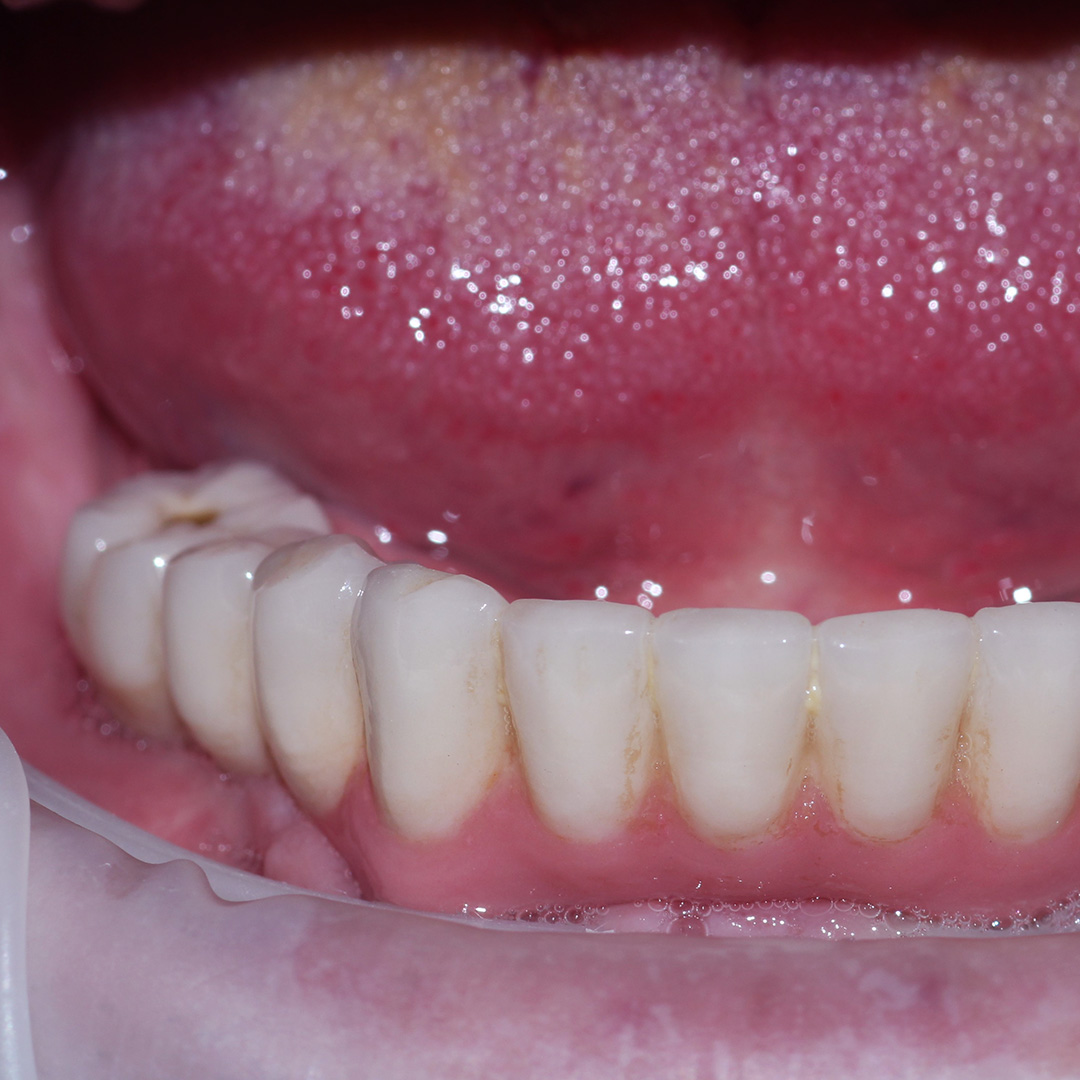

До и после лечения

В нашу клинику обратился пациент с жалобами на полное отсутствие зубов на нижней челюсти.

Осмотр проводил врач стоматолог-ортопед и хирург Мельников Алексей Владимирович. После консультации, совместно с пациентом, было решено провести протезирование по технологии All-on-4.

Методика позволяет восстановить зубной ряд на 4-х имплантах, установленных по определённой технологии. Протез при этом фиксируется сразу после имплантации.

В ходе процедуры были проведены следующие работы:

- профессиональная гигиена полости рта;

- изготовление протеза на основе предварительно созданной модели;

- вживление имплантов;

- фиксация протеза.